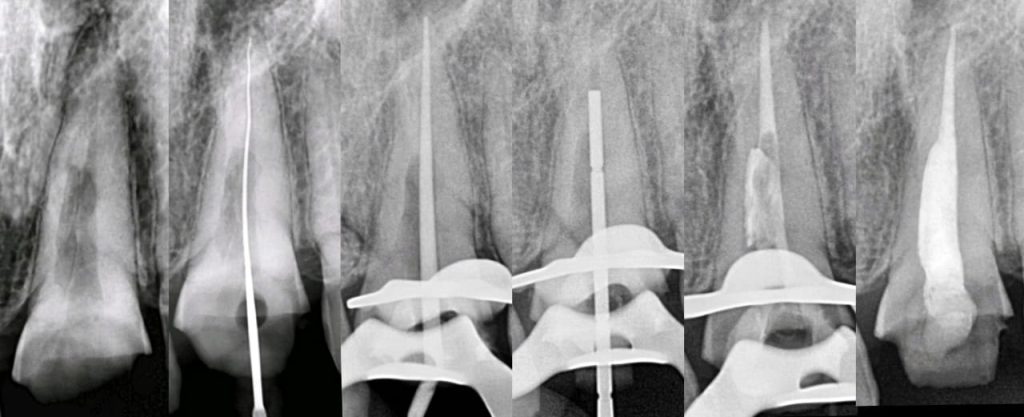

Clinically , IRR may go unnoticed until detected radiographically. However traditional radiographs can miss early lesions, whereas CBCT offers precise three-dimensional evaluation, especially in complex or perforated cases. Histologically, resorptive areas may show granulation tissue or bone-like deposits depending on the type. Management focuses on eliminating the pulp tissue and sealing the resorptive defect using advanced techniques such as warm gutta-percha, bioceramic sealers , or regenerative protocols when perforation is present.